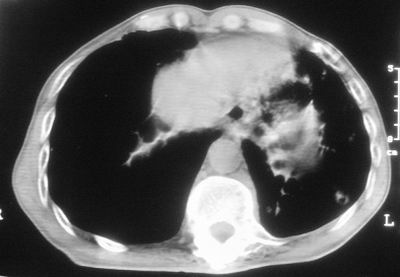

标题: CT11864:男,47岁,反复咳嗽、咯痰、咯血3年,请分析. [打印本页]

患者,男,47岁,反复咳嗽、咯痰、咯血3年,再发5天。痰培养未找到真菌、抗酸杆菌、癌细胞。

左肺上叶体积明显缩小,其内见多发透光区,纵隔向左侧移位,左肺下叶多发班片状病灶,边界模糊,1左肺上叶先天肺发育不全,2左肺下叶肺炎,

左肺上叶结核伴肺纤维化,纵隔移位,左肺下叶感染性病变,建议抗炎抗结核后复查,双肺气肿.

以下是引用xulianj在2008-2-25 21:01:00的发言:[br]左肺上叶结核伴肺纤维化有霉菌球形成,纵隔移位,左肺下叶感染性病变,建议抗炎抗结核后复查,双肺气肿.

考虑:左肺慢纤伴霉菌球形成、双肺全小叶型肺气肿。

1)考虑为:左肺上叶肺结核(空洞形成),伴左下肺感染;不排除霉菌感染可能。2)肺气肿。

左肺上叶结核伴肺纤维化空洞形成并左肺下叶感染,纵隔牵拉移位,建议作进一步检查排除左侧肺霉菌感染可能。